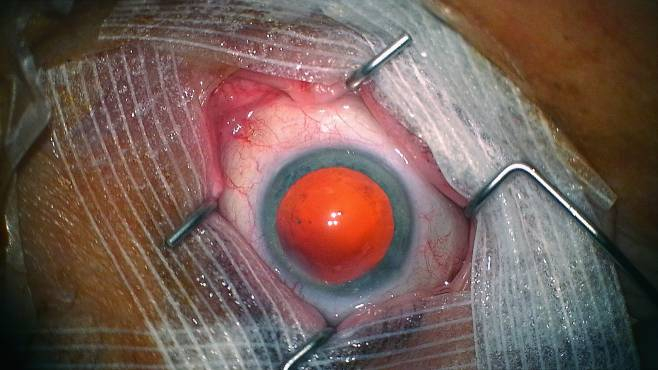

两个医生用结肠透镜在病人体内穿行,画面上呈现出被内窥镜摄像头强制打光而泛着异样光泽的肠壁黏膜,结缔组织如同超现实的红色花朵层层绽开;而操作手术的医生将幽深的肠道比作巴黎地铁,按顺序报出站名并探讨沿线的房屋价格——这一略带残忍的黑色幽默很大程度上得益于一种语言学张力,“tube”兼具三层意义,“管道”、“地铁”和“电视(显像管)”,这个词汇将管状物、历时感和视觉关联到一起,并且延续和总结了韦雷娜和吕西安影像构成的重要视觉特性。

《香草》(Sweetgrass, 2009)中的低照度摄影使得画面的传达受阻,“不合格”的图像使视觉信息退居其次,长焦镜头伸向并扫过黑夜中的被摄物,使得画面及其运动带上了一层触觉特质。《利维坦》(Leviathan, 2012)中对微型运动摄像机GoPro的运用,图像工具附着在自然生物或人造物表面, “搭乘”并产生一系列图像,这种附着不仅仅呈现了运动,也呈现了其存在状态和生命质感;《梦呓》(Somniloquies, 2017)对这一极端视角进行了提纯,手持摄影机在近乎全黑的睡眠情景下更近距离“抚摸”熟睡的人身体表面,摄影师的呼吸和脉搏通过手臂传导赋予镜头,同被摄物者的呼吸韵律混合,伴随着低照度下的慢门摄影产生的果冻效果,给予沉睡中的主体鲜明的造型和富有节奏的形变。《食人录》(Canibal, 2017)中的摄影机则被引入了一种充满“惰性凝视”的长焦摄影,以失焦和“跟丢”模拟触觉在身体上的阻滞和迟疑,并将这种阻滞和迟疑即时景观化。图像机器对主体表面的抚摸和爬行,对于物体的迫近和贴合欲望最终在《人体的构造》中突破了物体表面的限制——图像机器终于透过皮肤,进入到人体内部——以往作品中运动轨迹的顶部空间终于闭合,完成并呈现出了一种管状视野(tubular vision)。两人以往“搭乘”物体而构建的运动轨迹(本片“搭乘”的是医疗器械的成像系统以及医生对其进行的操作)是一种非人为直接干涉成像行为的“即时影像档案”方法。这种影像方式同样也意味着一种“被动成像”,将拍摄行为更多地指向和转化成一种收集行为。

如果说冈瑟·冯·海根斯(Gunther von Hagens, b.1945)在塑化的人体模型中展示的是一种人体的牵引机制和力学图景,那么韦雷娜和吕西安则将视野带进幽深的人体内部,试图一窥其与外界的传输交换体系的同时,在视觉上使其靠近并获得一种曼托瓦公爵宮 (Palazzo Ducale di Mantova)的顶画般的错觉和视觉交互方式,人体器官内部如同《利维坦》中的鸟群,《梦呓》中低照度的人体般,呈现出一种带有仰角透视法(di sotto in sù)的错觉绘画(pittura illusionistica)般的图像肌理——不仅仅体现在一种对“贴合”的极端视角的遵循,也需要图像在持续“穿行”的动作中持续产生——将运动和图像贯穿在一起的是图像即时形成和变化的历时感。管道中的影像只存在“里”和“外”的方向维度,在这个空间体系下,位置、深度和表层的概念被颠覆,图像的时间、地点和行为实现了一致的同步率,也组合并带来一种综合却陌生的感官体验。

这种虚幻的观感(至少对影院的观看者而言)是内窥镜图像在一种“全然真实”的技术追求下获得的,内脏的景观看上去仿佛是由计算机建模构成的三维动画(内脏同城市建筑不同,人类往往需要从虚构的视觉记忆库中寻找参考)。“贴近-透过-穿行”的图像在新媒体影像作品中经常被使用(其图像轨道通常是计算设计而成的),虚拟的摄影机透过破碎的人体表面到达皮肤贴图下的空无,其目的往往是为了呈现一种“错误”且疏离的空间。皮肤之下的“有”和“无”,“真实”和“虚构”背后的核心问题仍然是人体的广义器官学(Organology)——在后人类时代,皮肤下的骨骼、血液、神经和器官究竟对人们意味着什么?它们是否存在?它们失去了哪些功能,又获得了哪些功能?谁真正拥有它们?——正如新冠疫情为我们提出的问题——“谁拥有你的肺部”?